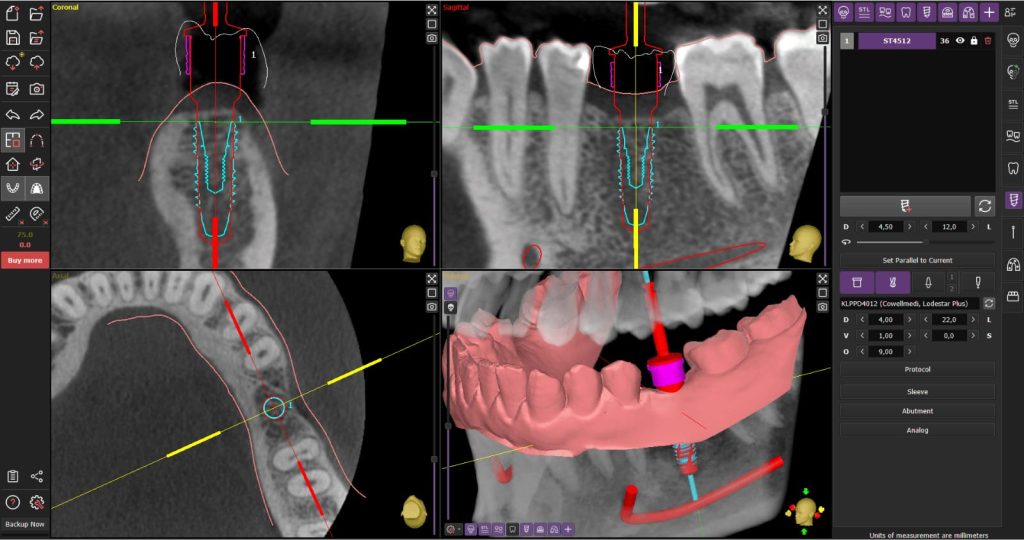

השתלה מונחית מחשב היא ביצוע הנחת שתלים על-פי תכנית דיגיטלית שנבנית מראש: מבצעים צילום CBCT, סריקה דיגיטלית/מודלים, מתכננים בתוכנה את מיקום/זווית/עומק השתלים ביחס לשיקום העתידי, ולאחר מכן מעבירים את התכנית לפועל באופן סטטי (תבנית מודפסת/מכורסמת שמדריכה את הקידוח וההכנסה) או דינמי (ניווט בזמן אמת בעזרת מצלמות/חיישנים). השרידות של שתלים שהונחו בהכוונה דיגיטלית דומה לשיטות “חופשיות” כאשר נבחרים מקרים מתאימים ומתבצע פרוטוקול נכון.

- CBCT + סריקה דיגיטלית/מודלים → מיזוג נתונים, הגדרת עמדות שתלים, מולטי-יוניטים, וציריות ביחס לשיקום העתידי.

- בדיקת מרווחי בטיחות (2 מ״מ לפחות), מניעת קונפליקטים עם שורשים/תעלה/סינוס.

- סטטי: תבנית נתמכת-שן/מוקוזה/עצם; קיבוע פינים לפי הצורך; בחירה בין הדרכת פיילוט בלבד לבין Fully-Guided.

- דינמי: כיול מצלמות/סמנים, בדיקת דיוק על פי נקודות מוכרות לפני תחילת הקידוח.